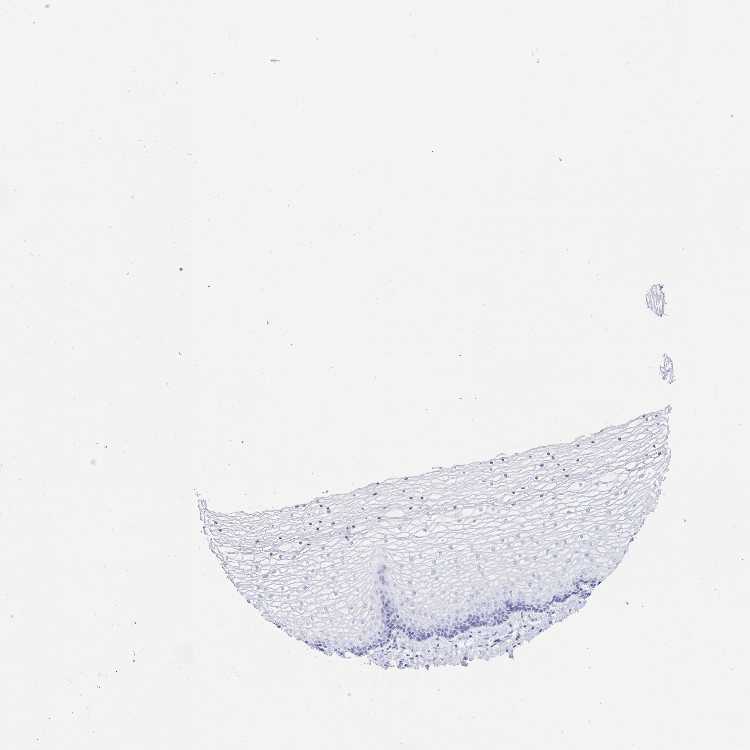

VAGINA - Antibody stainingi

Antibody staining in the annotated cell types in the current human tissue is reported as not detected, low, medium, or high, based on conventional immunohistochemistry profiling in selected tissues. This score is based on the combination of the staining intensity and fraction of stained cells.

Each image is clickable and will lead to virtual microscopy that enables deeper exploration of all samples and also displays staining intensity scores, fraction scores and subcellular localization as well as patient and tissue information for each sample.

Antibody HPA062915

Squamous epithelial cells Not detected